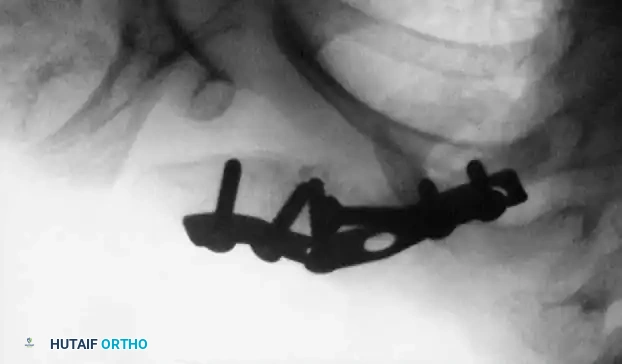

Fig. 33-98B: Postoperative radiograph following open reduction and internal fixation. At surgery, fibrous tissue and rudimentary callus were excised. Rigid fixation was achieved using a semitubular plate, leading to successful osseous union.